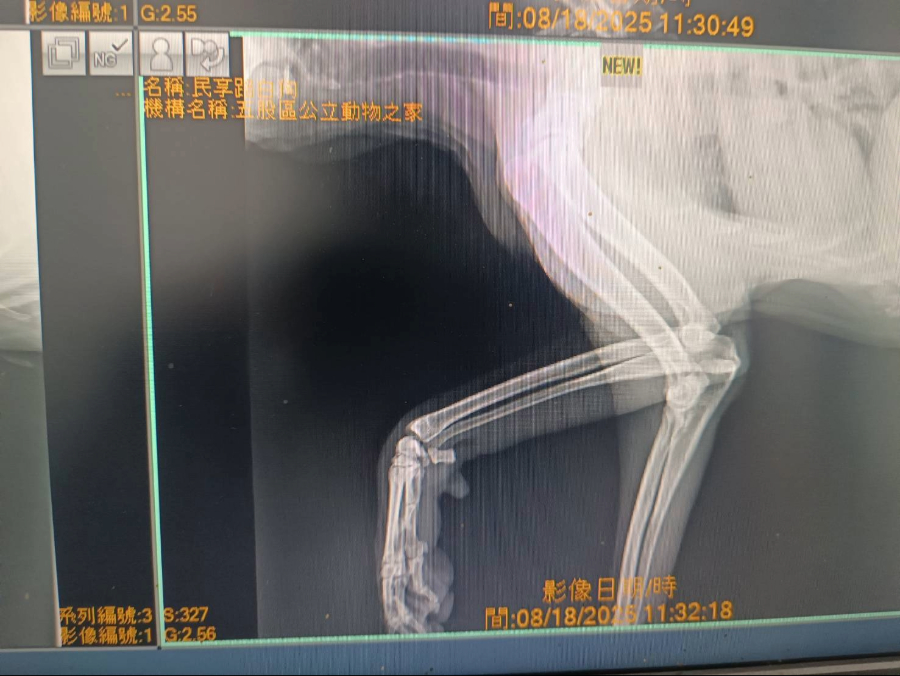

在接獲民眾通報後,動保處人員立即趕赴現場,發現大黃弟的前腳潰爛嚴重、深可見骨,推測已疼痛多時,仍努力行走覓食,救援人員小心將牠送往五股動物之家,獸醫師立即進行清創、包紮、投藥及X光檢查,確認傷勢未波及骨頭,經過多日細心治療與營養補充,大黃弟的傷口逐漸癒合,體力與精神明顯恢復許多,原本緊張的行為也漸漸變得比較親近人,願意與人互動相信人類。

醫療檢查中